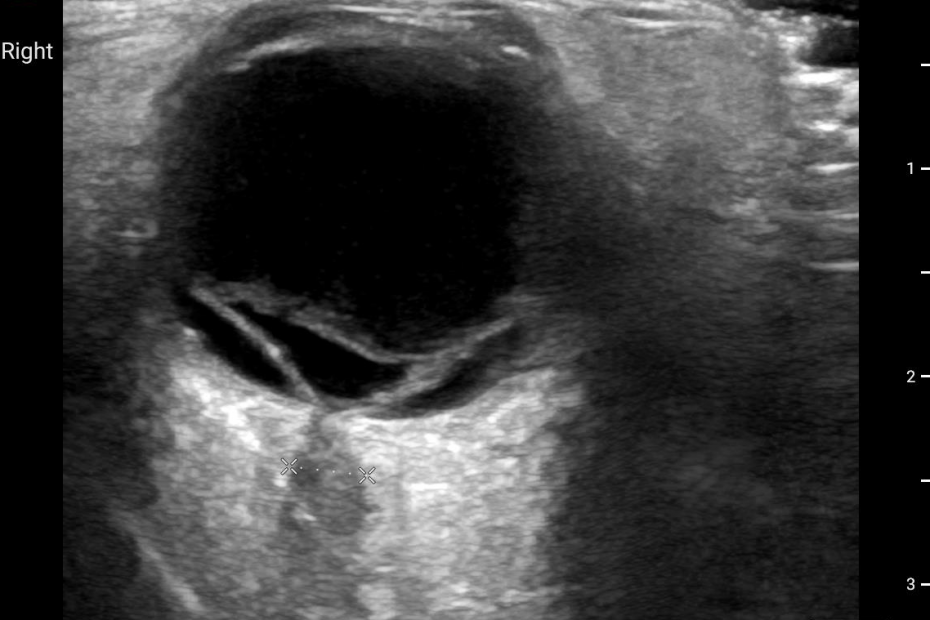

Retinal Detachment 01